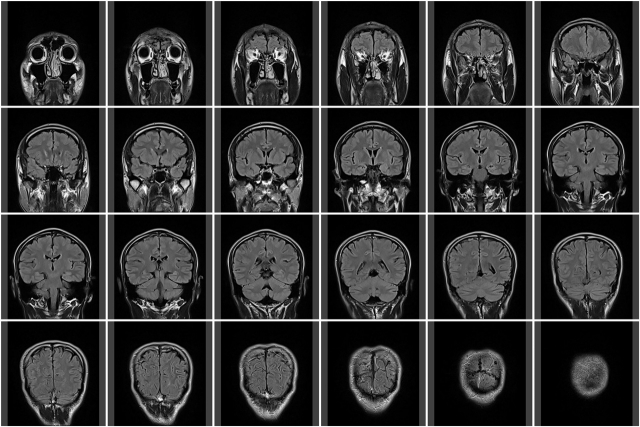

で、席につくと医師が写真を見ながら説明を始める。

MRIとCTと写真を撮ったが、紹介状に書かれていたような症状の原因は何も見つからなかったとのこと。

「ここに白い跡があるんですよね、脳梗塞の跡のようですね。」

脳梗塞?そんな症状は最近なかったと思うが。。

いつ頃の跡なのかを訊ねてみたが、それは分からないという。

5年単位なのか10年単位なのか不明だという。

脳梗塞、、つまり脳内で血管が切れて出血した跡ということになるのだが、必ずしも明確な症状が出るわけではないという。

今後の生活に直接影響が出るわけではないが、高血圧や糖尿病的な要素があると動脈硬化などから常に脳梗塞のリスクは抱えている状態と言えるとのこと。

そのリスクがどの程度とは定量的には表せないようだが、健康体の人よりはリスクは高いらしい。